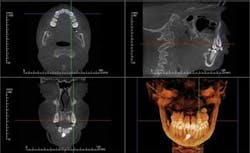

CBCT images can be modeled by Anatomage in the traditional form of digital study casts. They can then be viewed and morphed into desired tooth positions. The pre/post treatment CBCT scans can be superimposed showing the positional change between the two, which is actually 4D imaging (Figure 3). An animated, digital morph movie can be made to show the before and after morphing.